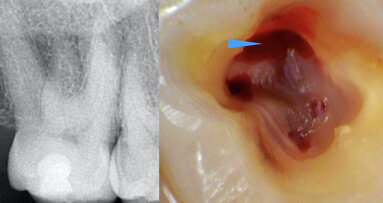

DUNDEE, Scotland: Management of irreversible pulpitis in permanent teeth is undergoing a gradual but meaningful shift. Advances in diagnostic understanding ...